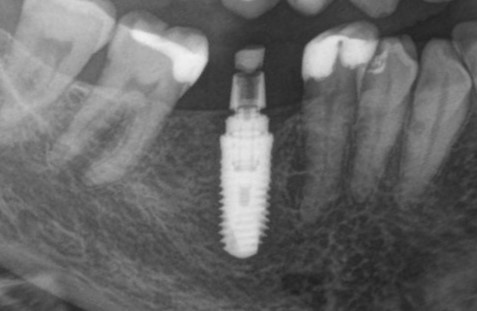

Для примера мы возьмём немедленную имплантацию:

Никогда, почти никогда нам не удаётся сохранить конфигурацию лунки удалённого зуба в первоначальном виде — вслед за удалением неизбежно следует атрофия краевой кости, которую мы деликатно называем «перестройкой» или «ремоделированием». Это совершенно нормальный физиологический процесс, о нём я подробно написал здесь>>, рекомендую почитать.

Так вот, из-за этой атрофии вокруг платформы имплантата остаётся фиброзный ободок, видимый на снимке:

В таком состоянии он остаётся много лет, не вызывая какого-либо беспокойства у пациента. Однако, для некоторых докторов он является поводом начать разговор о несостоятельности имплантата — «патамушта ета периимплантит». Хотя, я повторюсь, какая-либо воспалительная симптоматика и здесь отсутствует, в принципе.